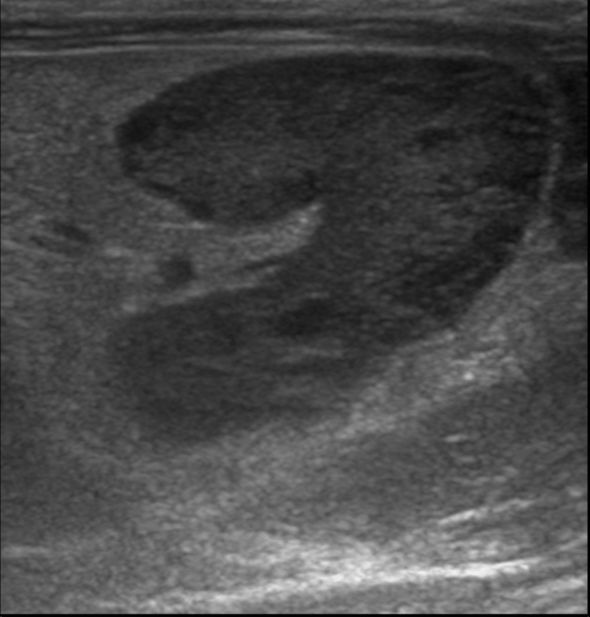

Lorsque les glandes surrénales sont fortement stimulées, elles deviennent progressivement hyperplasiques puis tumorales (tumeur bénigne puis maligne). Le diagnostic peut être établi par échographie, réalisée par un vétérinaire expérimenté avec les furets, et par une prise de sang (dosage des hormones en question). Suivant l'extension et la présence ou non d'embole vasculaire, il est recommandé de poser un implant hormonal ou de réaliser une surrénalectomie. Cette chirurgie est particulièrement risquée à cause de la proximité des glandes surrénales avec l'aorte, un vaisseau sanguin vital pour l'organisme. Il peut être utile d'utiliser des outils de microchirurgie ainsi que du matériel de pointe tel qu'une caméra endoscopique per-opératoire Vitum pour maximiser la réussite de la chirurgie.

Le diagnostic se fait par prise de sang et par échographie, réalisée par un vétérinaire expérimenté. Parfois, un traitement doit être administré en urgence, car les crises d'hypoglycémie peuvent être mortelles. Une hospitalisation est nécessaire en cas de crises convulsives. Les premières phases du traitement sont médicales mais une chirurgie (pancréatectomie) peut être recommandée dans certaines formes d'insulinome. Nous utilisons pour ce faire la technologie Ligasure pour minimiser le temps opératoire et les risques associés à l'opération.